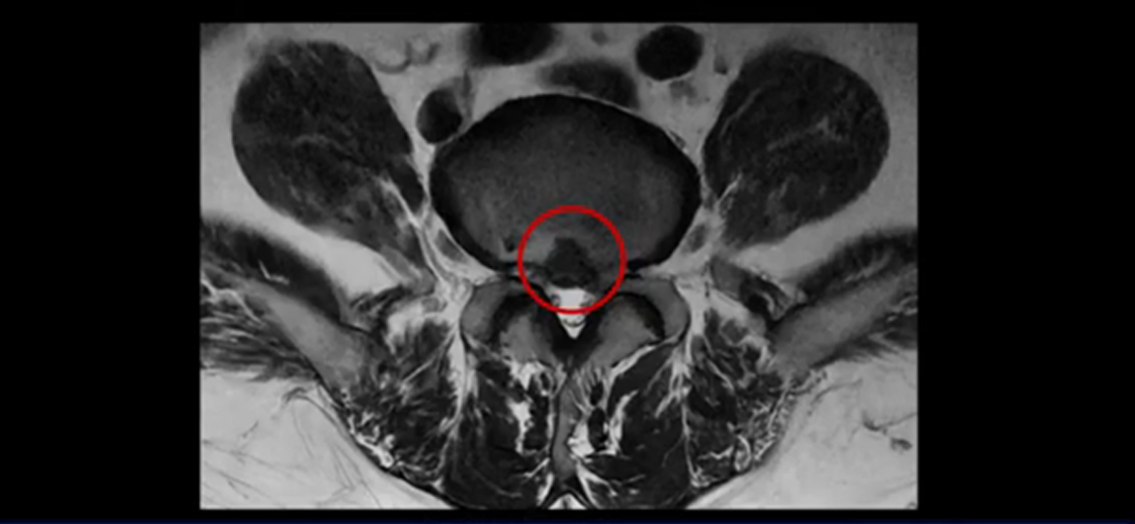

그런데 이분은 4번 5번에도 디스크 파열이 있습니다.

가운데로 심하게 밀려 나와 있는데요.

또 4번 5번에는 협착으로 척추관이 많이 좁아져 있습니다.

또 왼쪽 신경 가지들이 빠져 나가는 신경구멍들이 여러 마디가 좁아져 있습니다.

이런 이유들 때문에 왼쪽 엉덩이부터 종아리, 발가락까지 저리고 아픈 겁니다. 그래서 서둘러 병원에 가셨는데요. 그래서 서둘러 병원에 가셨는데요. 여러분이 꼭 아셔야 할 게 이렇게 다리가 심하게 저리고 아프면 X-ray만 찍을 게 아니고 MRI를 찍어 보시는 게 맞습니다. X-ray로는 디스크가 터졌는지 신경구멍이 좁아진 협착이 있는지를 정확히 할 수가 없습니다. 그래서 이분은 당장 아픈데 해결이 안 되니까 제주도에서 유명하다는 한의원으로 갔습니다.